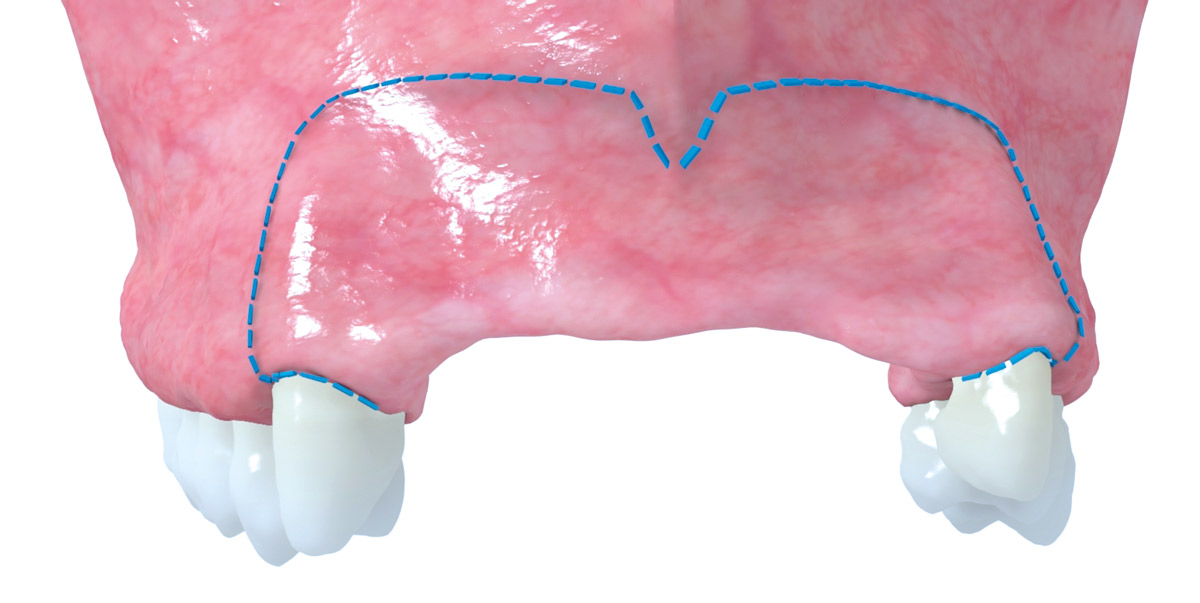

3/17 - Complex bone defect with partial loss of the buccal wall after implant extractionRestoration of all four incisors with maxgraft® bonebuilder - Dr. Dr. Dr. O. Blume

5/17 - Virtual three-dimensional reconstruction of the defect and bone block designRestoration of all four incisors with maxgraft® bonebuilder - Dr. Dr. Dr. O. Blume